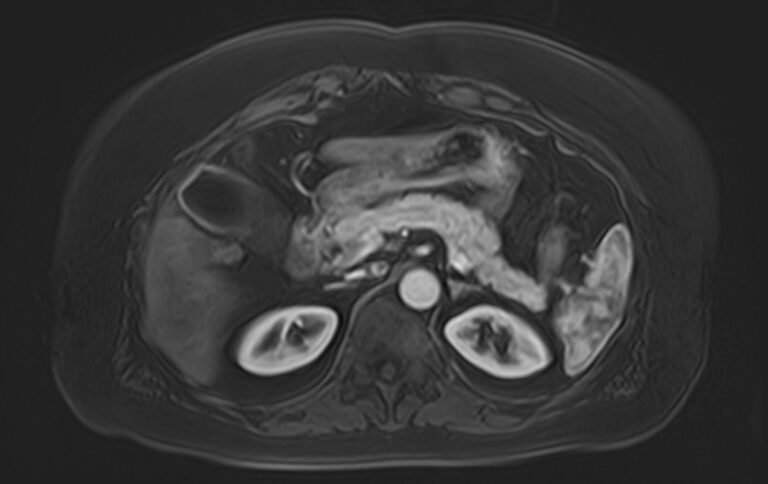

• Доброкачественные образования (кисты, гемангиомы, аденомы) и злокачественные опухоли органов брюшной полости (первичные опухолевые очаги и метастатические поражения, в том числе, брюшины).

• Заболевания печени (жировая инфильтрация печени, гепатиты, цирроз и др).

• Заболевания желчного пузыря и желчевыводящих протоков, поджелудочной железы (желчекаменная болезнь, холецистит, панкреатит и др).

• Патологическое скопление жидкости в брюшной полости (асцит).

• Паразитарные и глистные инвазии (эхинококкоз, аскаридоз и др).

• Наследственные патологии и аномалии развития (гипоплазия печени, атрезия желчных протоков, наследственные гепатозы и др).

• Портальная гипертензия на фоне заболеваний печени.

• Травматические повреждения органов брюшной полости.